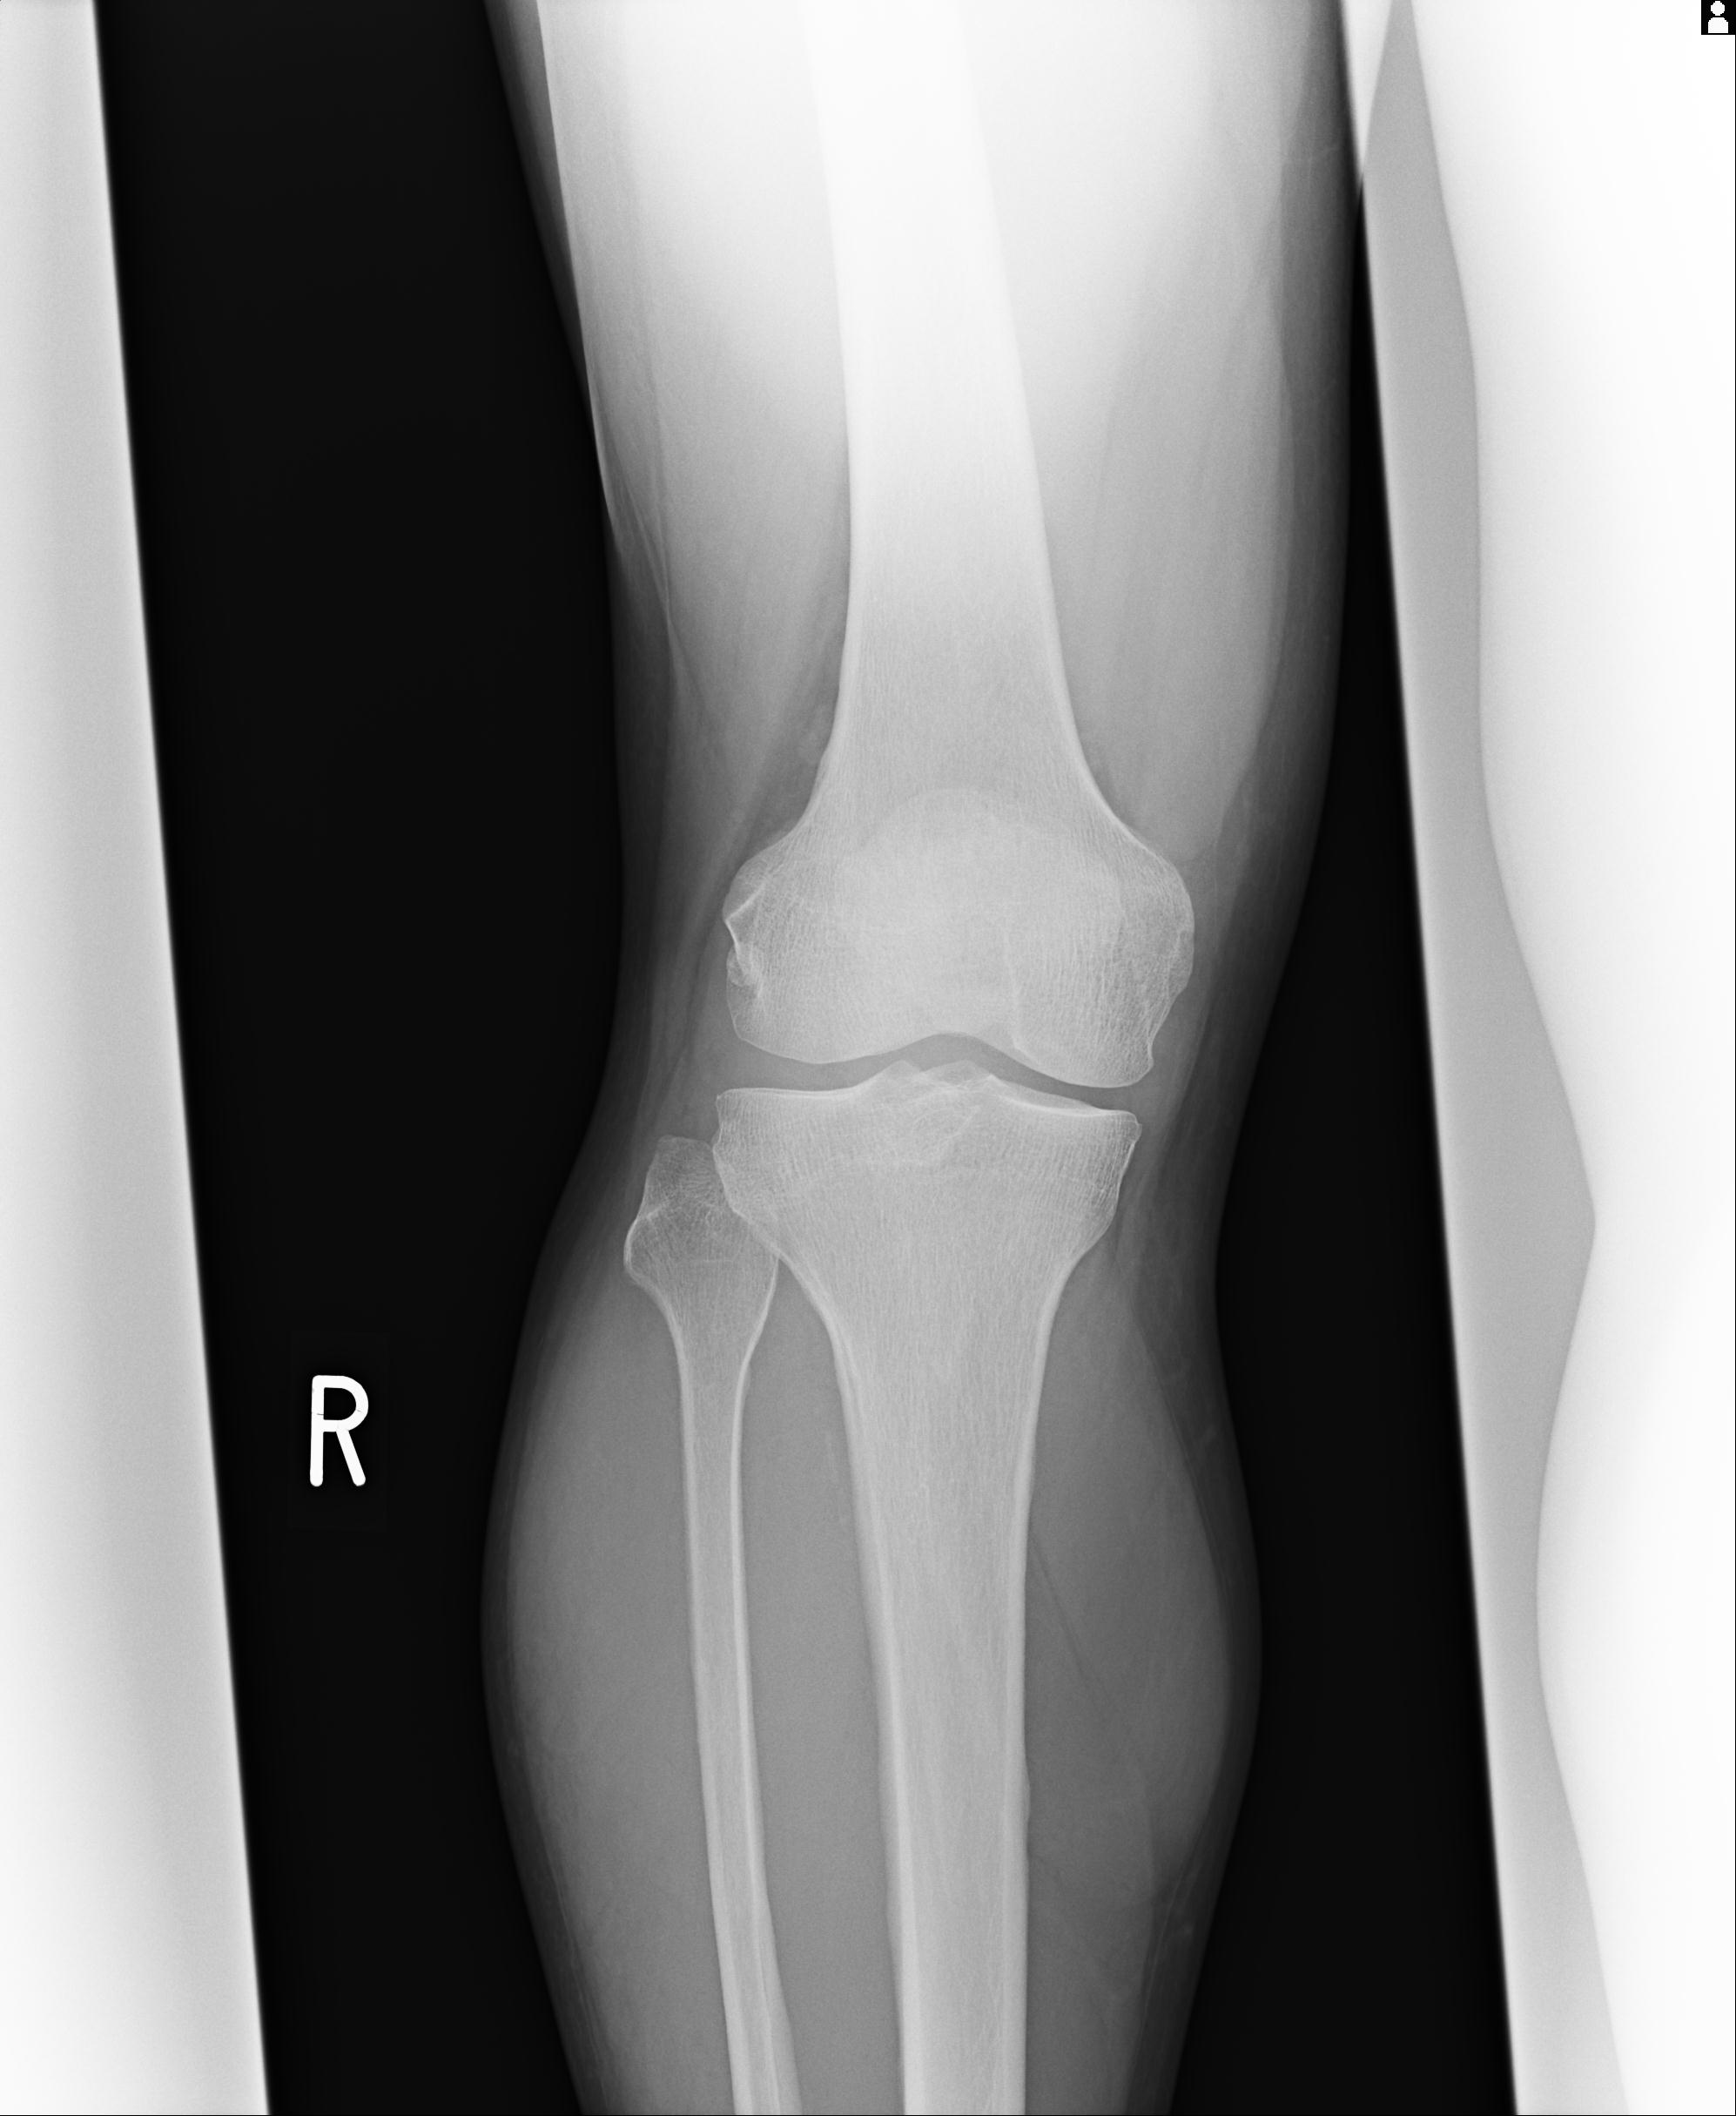

49554 3/13 膝 4R 3/16 4R 1/18 2R 78歳男性 膝蓋骨骨折